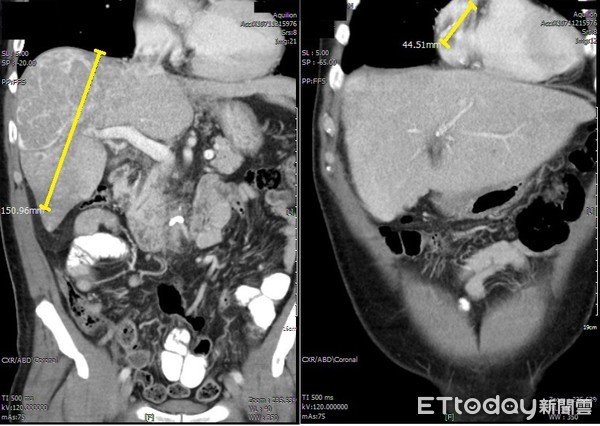

▲肝癌腫瘤長大到15公分(左),甚至還侵入右心房(右)。(圖/亞洲大學附屬醫院提供)

王博民指出,惡性重大的肝癌腫瘤每40天會長大一倍,有C肝病史的民眾,更應每三個月回診接受超音波及抽血檢查,通常出現像該患者這樣的症狀--肝腫瘤約15公分大,加上延伸至右心房,使右心房也出現4公分腫瘤,多數狀況恐早已肝衰竭,而他應是長年保有運動習慣,使體力及免疫力較同齡者強,「否則無法支撐這麼久」。